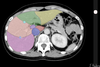

green:

pink:

yellow:

purple:

orange: segment II

green: segment IVa

pink: segment VIII

yellow: segment VII

orange: segment II

green: segment IVa

pink: segment VIII

yellow: segment VII

purple:

red: segment I